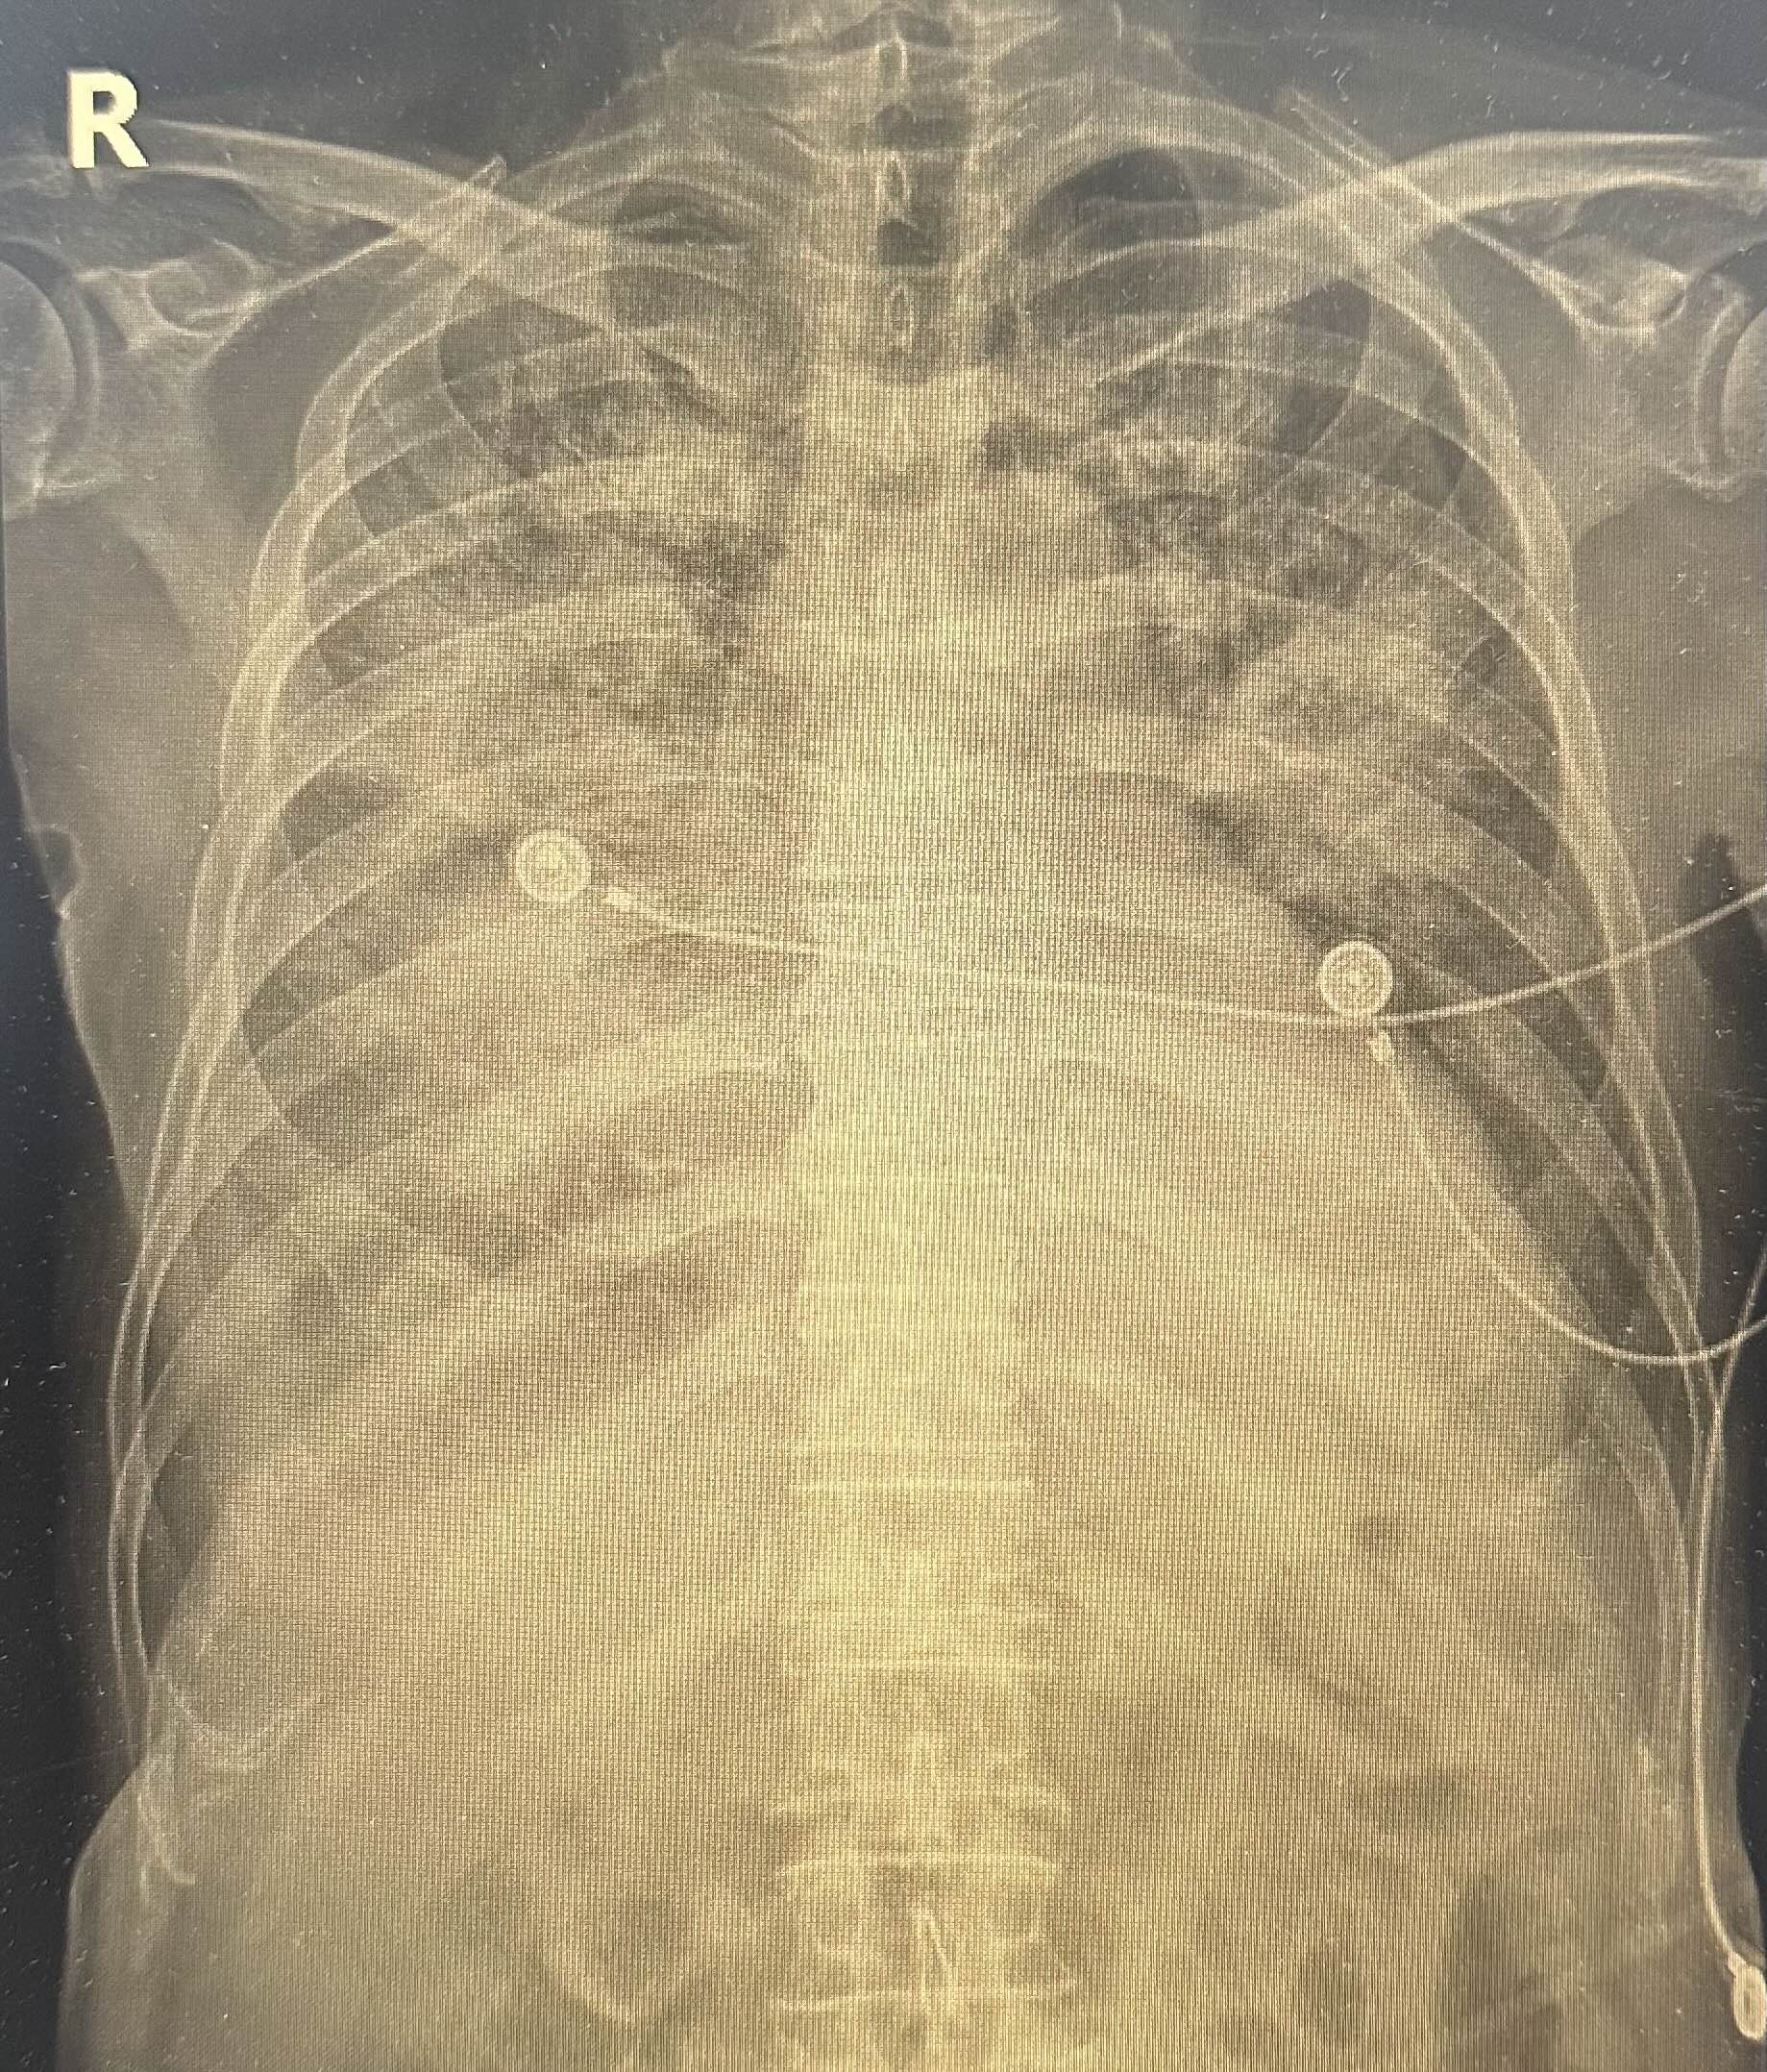

폐렴으로 입원치료를 한지 나흘째.. 호흡도 폐렴은 점차 심해져 급성 호흡곤란 증후군(ARDS)*과 같은 양상으로 나빠지고 있던 상태였다.

다만, 젊은 사람의 경우와는 달리 환자분의 지병과 폐렴의 기전(이환자의 경우엔 흡인성폐렴) 및 현재 x ray 등을 고려했을 때 호전되어 extubation을 하는 것은 쉽지 않아 보이며, 추후엔 기관절개술(tracheostomy)이 필요할 가능성이 높다는 설명을 드렸다.